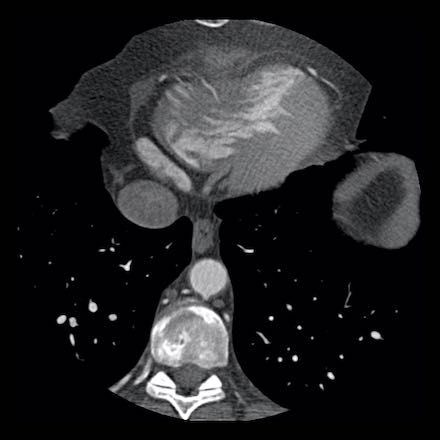

Same patient. First, study the CTA image.

How would you describe the findings?

The coronal image shows a central low-attenuation area around the lumen

of the LAD.

This low-attenuation area is surrounded by a higher attenuation

area.

This finding is the earlier discussed napkin-ring sign, which is a high-risk

plaque feature.

This patient classifies as CAD-RADS 4A/P1/HRP.